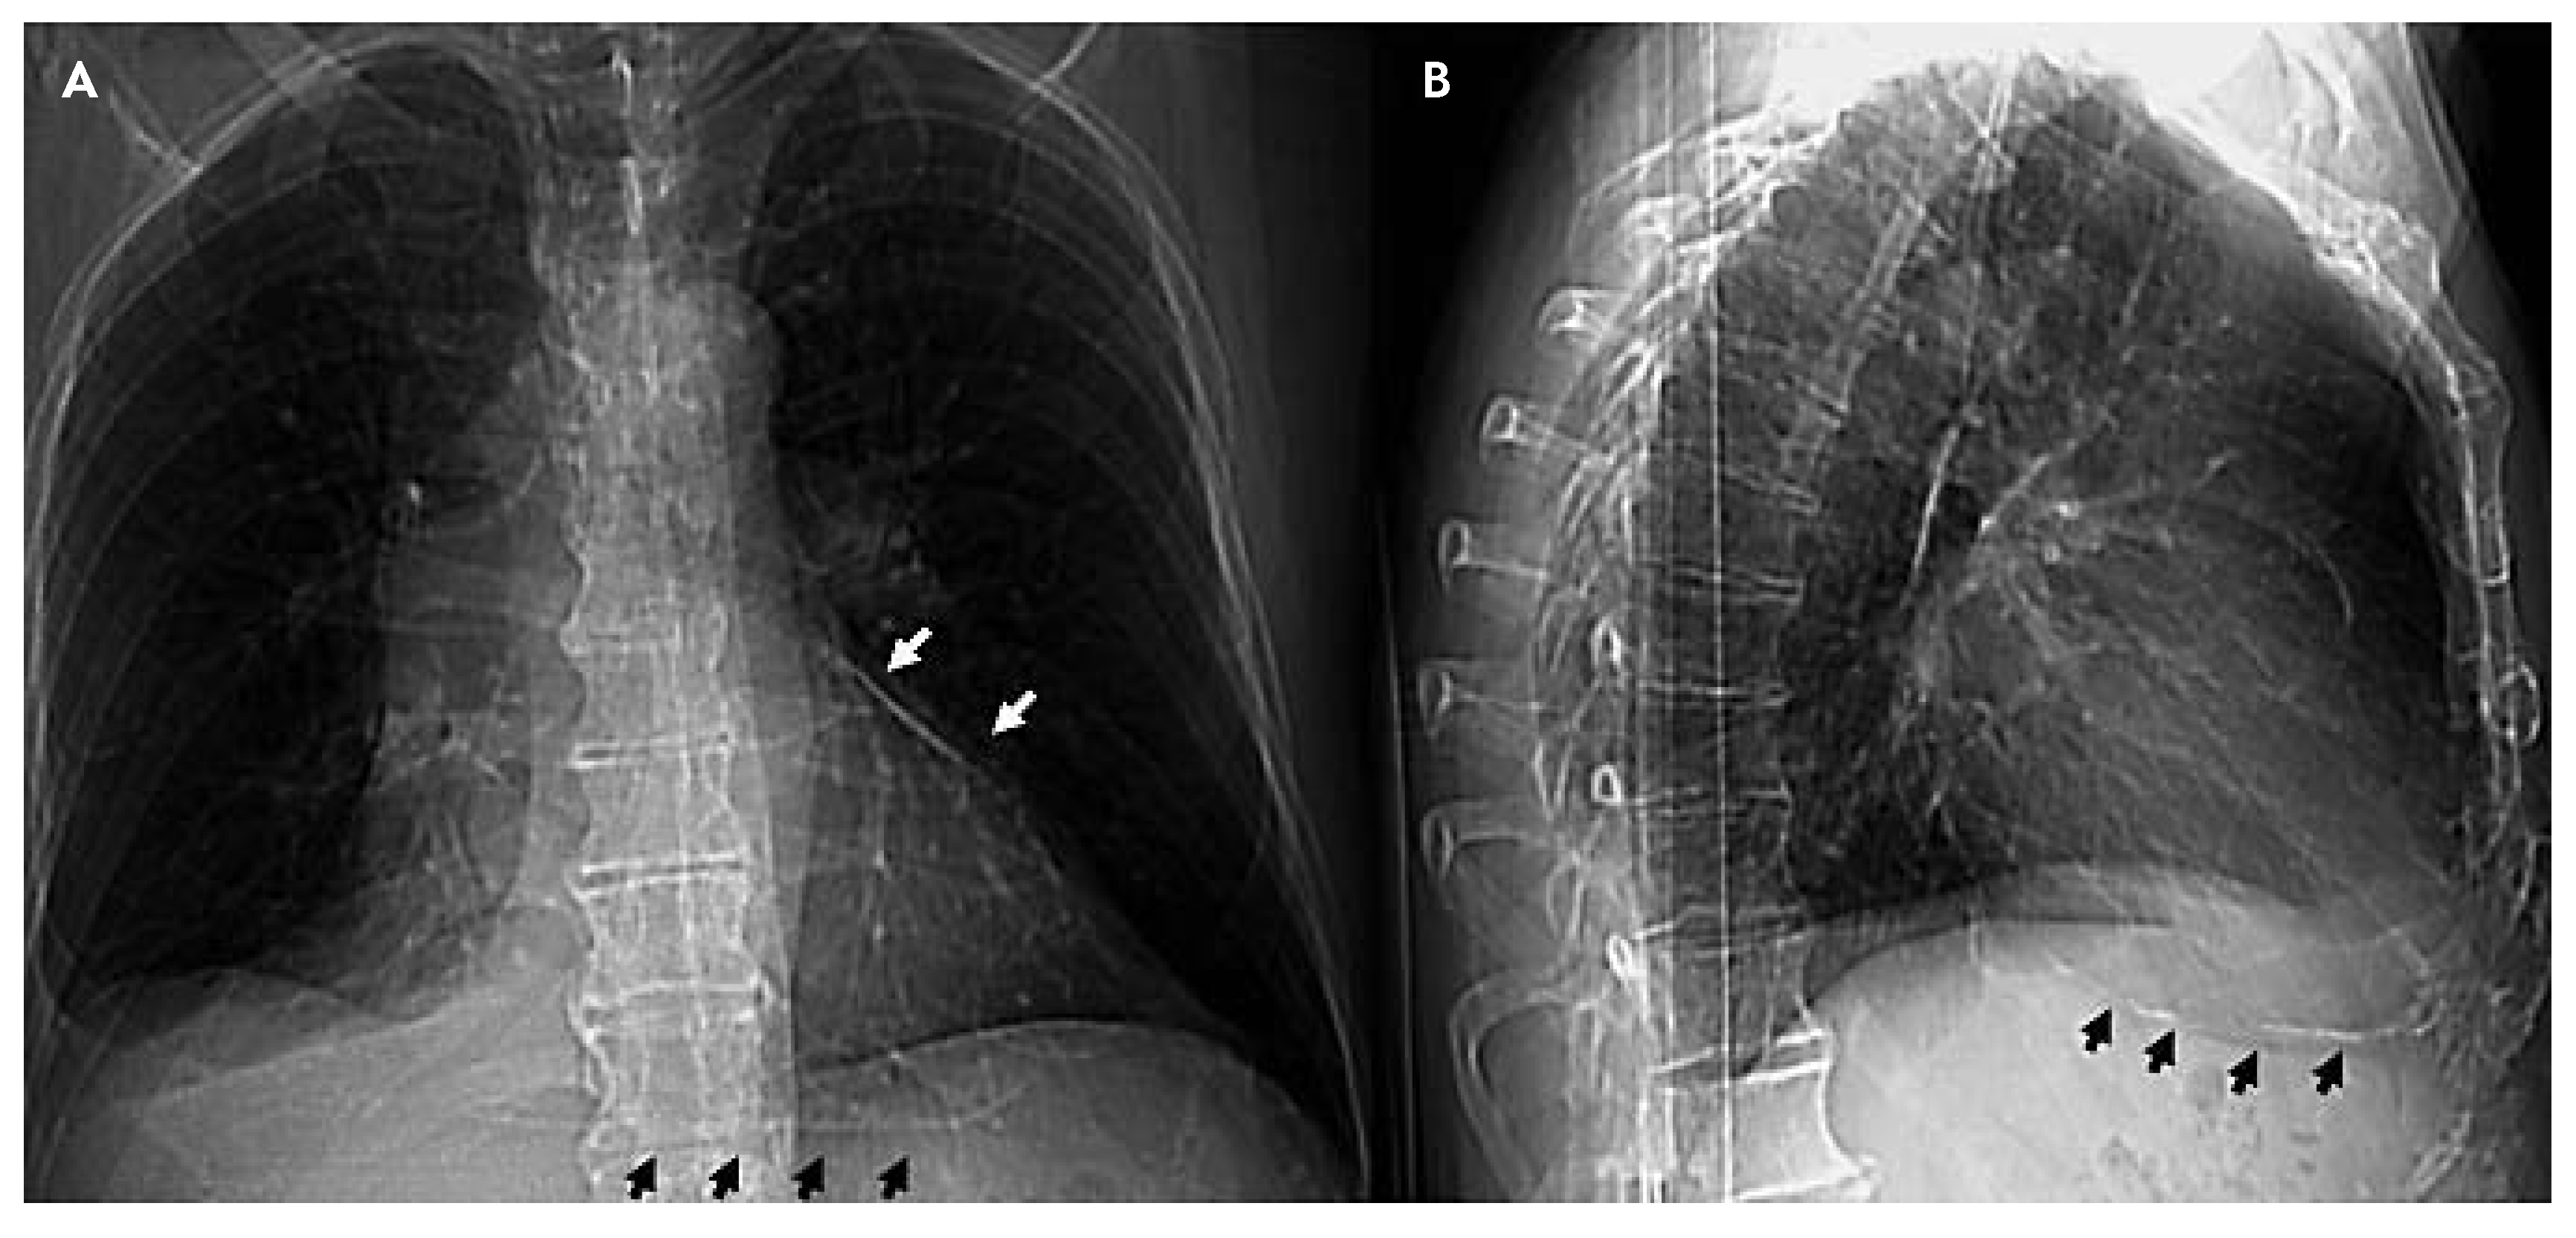

Chest X-ray (Figure 1A,B) shows diffuse pericardial calcifications and right pleural effusion. Thoracic CT scan confirms pleural effusion and circumferential pericardial thick-ening (6 mm) with calcifications (fig. 2A) together with dilatation of the inferior vena cava, hepatomegaly and ascites. 3-dimensional reconstruction (Figure 2B) nicely delineates the spatial extension of pericardial calcifications.

Figure 1. Chest X-ray (antero-posterior and lateral view): pericardial calcifications (black and white arrows) and right pleural effusion.